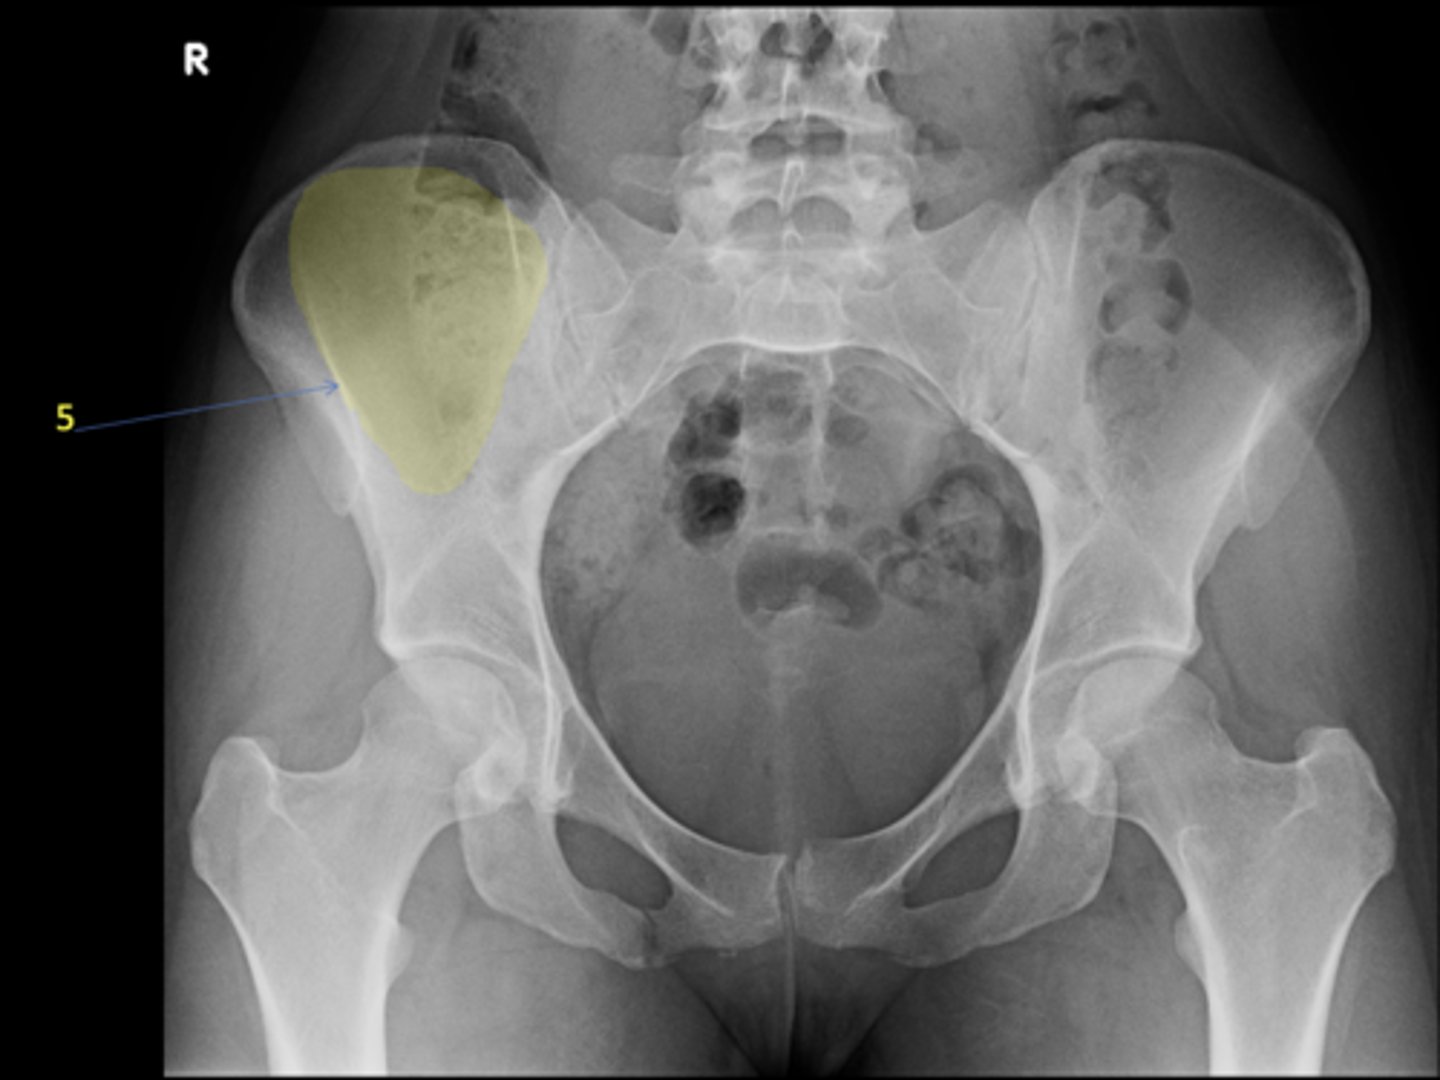

1

AP pelvis

5

Right iliac fossa

<p>ID 5</p>